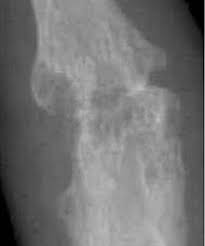

If the pattern of disease is not symmetrical, then a different diagnosis should be considered. Imaging tests you may get. The 2010 rheumatoid arthritis classification criteria help doctors diagnose rheumatoid arthritis. The ulnar styloid is destroyed with the rest of the distal ulna (white arrow), there is destruction of the carpal bones (yellow arrow) and there is dislocation of the 1st metacarpal on the destroyed trapezium. It can affect anyone of any age. Rheumatoid arthritis (ra) is a chronic autoimmune multisystemic inflammatory disease that affects many organs but predominantly attacks the synovial tissues and joints. Rheumatoid arthritis affects around 400,000 adults aged 16 and over in the uk. Rheumatoid arthritis can be difficult to diagnose because many conditions cause joint stiffness and inflammation and there's no definitive test for the condition. Ra causes pain, swelling, stiffness, and loss of function in joints. Rheumatoid arthritis is an inflammatory arthritis affecting both small and large joints in a symmetric distribution. Rheumatoid arthritis is an immune system condition, or autoimmune disorder, that causes inflammation of the lining of the joints. Rheumatoid arthritis is a chronic inflammatory disorder that can affect more than just your joints. Rheumatoid arthritis manifests as a symmetrical arthritis, most commonly affecting the hands.

If the pattern of disease is not symmetrical, then a different diagnosis should be considered. In rheumatoid arthritis, the body's immune system attacks its own healthy cells inside certain joints, leading to an inflammatory response. For more information and past images of the month, go to. However, they are not useful in the early stages of rheumatoid arthritis, before joint damage occurs. </b>rheumatoid arthritis (ra) is a polyarticular disease with bilateral and symmetric distribution. Sorptiometry should be performed to diagnose. The rheumatoid community on reddit. Rheumatoid arthritis (present for >10 years). The ulnar styloid is destroyed with the rest of the distal ulna (white arrow), there is destruction of the carpal bones (yellow arrow) and there is dislocation of the 1st metacarpal on the destroyed trapezium. Rheumatoid arthritis affects around 400,000 adults aged 16 and over in the uk. Reddit gives you the best of the internet in one place. Ra causes pain, swelling, stiffness, and loss of function in joints. The earliest manifestation of rheumatoid arthritis of the forefoot is synovitis of the mtp joints with eventual hyperextension deformity of the mtp joints including distal.

It is caused when the immune system (the body's defense system) is not working properly. Rheumatoid arthritis is a chronic inflammatory disorder that can affect more than just your joints. Rheumatoid arthritis is an immune system condition, or autoimmune disorder, that causes inflammation of the lining of the joints. Rheumatoid arthritis (ra) imaging tests are used to look for signs of ra and to monitor the disease's progression. For more information and past images of the month, go to. Reddit gives you the best of the internet in one place. These tests primarily look for bone damage in the patient's joints caused by the inflammation associated with ra. Rheumatoid arthritis manifests as a symmetrical arthritis, most commonly affecting the hands. Rheumatoid arthritis can be difficult to diagnose in its early stages because the early signs and symptoms mimic those of many other diseases. Ra causes pain, swelling, stiffness, and loss of function in joints. Rheumatoid arthritis is considered an indication for resurfacing of the patella during total knee arthroplasty. Imaging tests you may get. It can get worse quickly, so early these can be used to diagnose rheumatoid arthritis and check how the condition is developing.